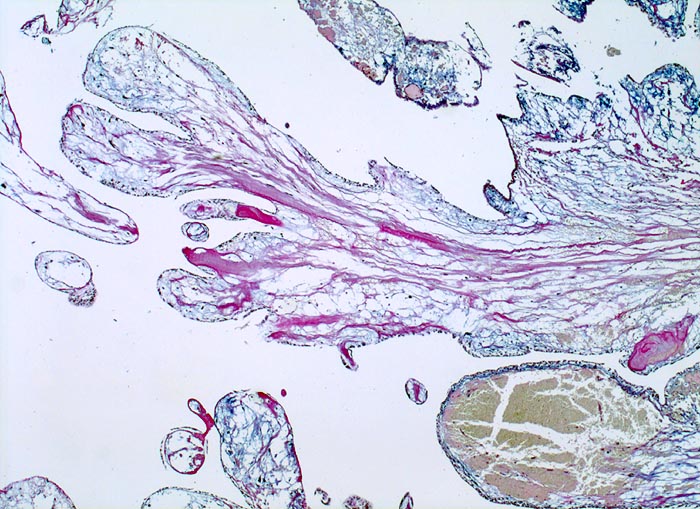

PathoPic ID 3004 - Vorhofmyxom

Vorhofmyxom

benigner Tumor

Herz Vorhof

Kardiovaskuläres System

Papillär gebauter Tumor mit ödematösem myxoidem Stroma. Fokale Stromablutungen.

Histologie

25